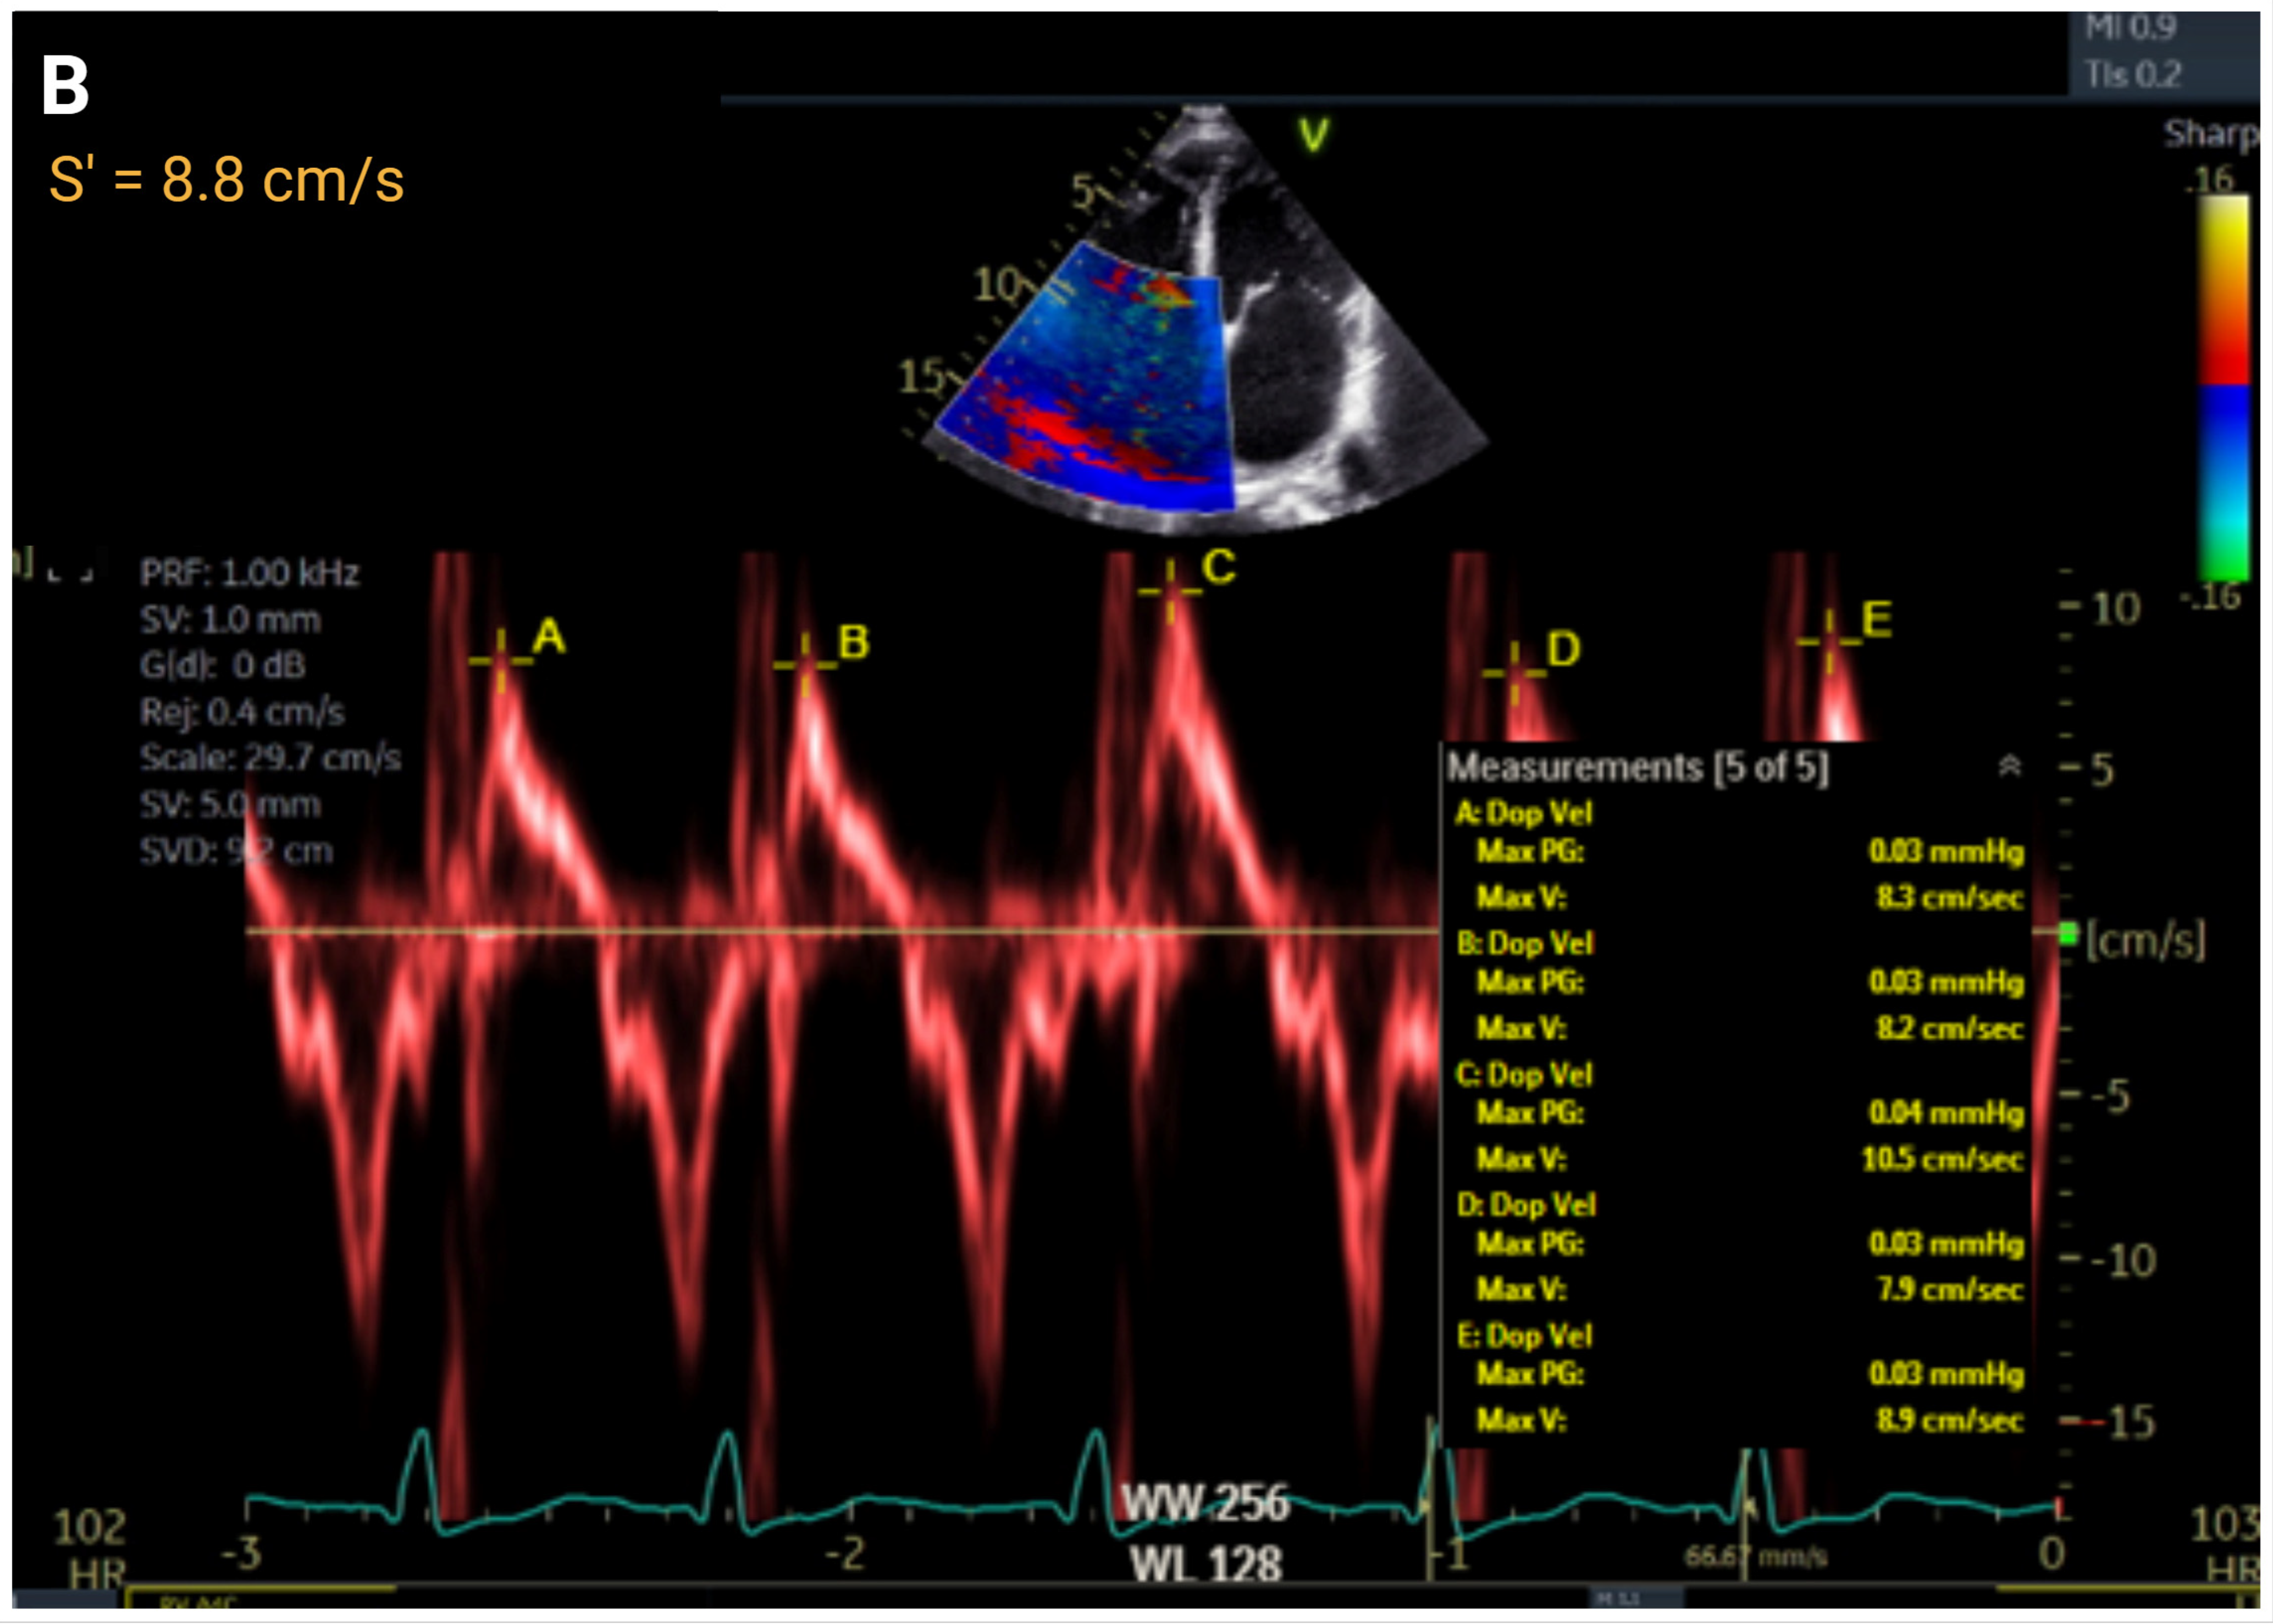

| Right Ventricular Systolic Function | ||||||

| S′, cm/s | >9.5 | ≤9.5 to ≥7.2 | ≤7.2 to >5.0 | ≤5 | r = 0.36 to 0.52 | |